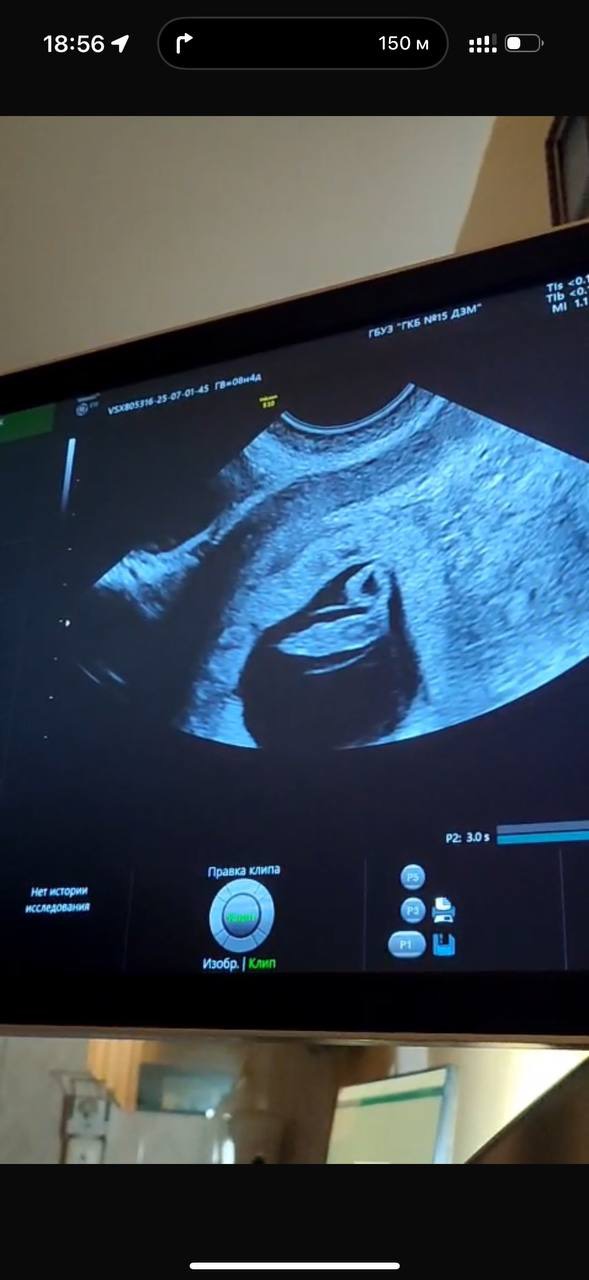

А вот и фото с УЗИ 😍 я даже поверить не могу, что это уже целый организм с бьющимся сердечком, проявляющимися ручками и головой 🥹

Огромное спасибо 😊 когда мне показывали ручки, и показали как бьется сердце , я не верила, что это во мне 🤰🏼 поначалу даже какой-то легкий страх был, но потом муж успокоил сказал «не дури, пойдем поедим нормально»))) а то мы же спортсмены с ним 😃 большое спасибо! Не буду! Даже кондиционеры не включаю лишний раз! И только 23-25 градусов !)